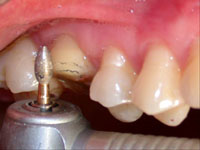

Fig. 3

Determinação do bisel chanfrado ou côncavo vestibular com a ponta diamantada n°3118 (KG Sorensen).

O ângulo cavo-superficial foi preparado com ponta diamantada (nº3118 da KG Sorensen) girando em baixa velocidade, formando um bisel chanfrado em toda extensão da margem vestibular e lingual do dente (Fig. 3). Por sua vez, as margens proximais foram biseladas com ponta diamantada de diâmetro menor (nº1111 da KG Sorensen) estendendo-se para vestibular e lingual com o intuito de manter o término cavitário separado do dente vizinho e manter a distância biológica horizontal (espaço para acomodar a papila sem ser comprimida, facilitar o acabamento das margens de esmalte, das bordas da restauração, a moldagem e o espaço para higienização) (Fig. 4 e 5).